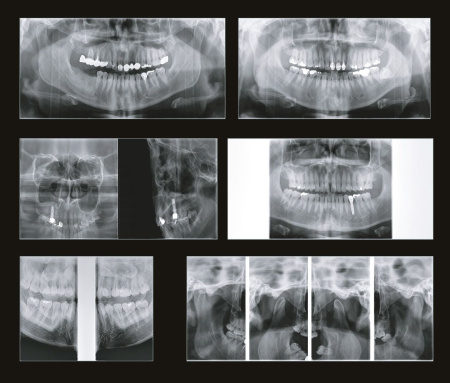

Панорама

Высокое разрешение при панорамной съёмке

Мульти фокус

Функция используется в режиме панорамы. Технология мульти фокуса позволяет добиться максимального качества, максимальной глубины резкости и захвата всей зоны сканирования при помощи пяти фокусных слоев.

Режим экспозиции панорамной съёмки

– Стандартный панорамный

– Ортогональный панорамный

– Сегментарный панорамный

– Горизонтальные и вертикальные сегменты

– Прямая проекция ВНЧС

– Детский панорамный

– Левый, правый ВНЧС в латеральной проекции

– Левый, правый ВНЧС прямая в латеральной проекции

– Синусы латеральная и прямая проекции

Панорама

Высокое разрешение при панорамной съёмке

Мульти фокус

Функция используется в режиме панорамы. Технология мульти фокуса позволяет добиться максимального качества, максимальной глубины резкости и захвата всей зоны сканирования при помощи пяти фокусных слоев.

Режим экспозиции панорамной съёмки

– Стандартный панорамный

– Ортогональный панорамный

– Сегментарный панорамный

– Горизонтальные и вертикальные сегменты

– Прямая проекция ВНЧС

– Детский панорамный

– Левый, правый ВНЧС в латеральной проекции

– Левый, правый ВНЧС прямая в латеральной проекции

– Синусы латеральная и прямая проекции